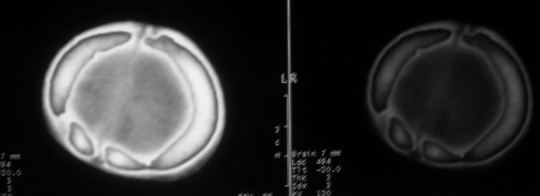

男,60天,发现头顶部囊性肿物2天。

考虑左侧顶骨皮样囊肿或表皮样囊肿。

考虑左侧顶骨皮样囊肿或表皮样囊肿,脑膜脑或脑膜膨出待排.建议冠扫